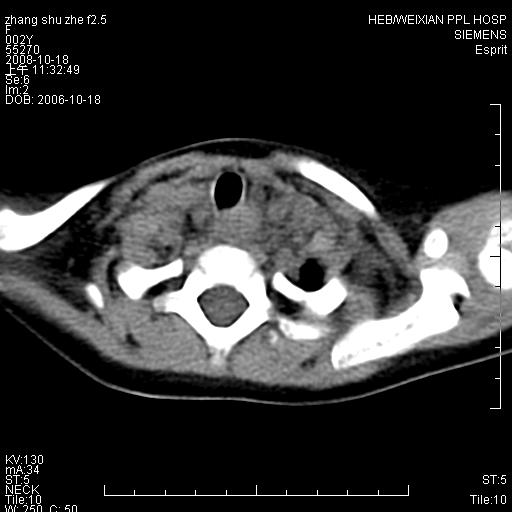

以下是引用dyqct在2009-2-10 21:04:00的发言:[br]年龄?性别?有发烧吗?[br]鼻咽部、口咽部、喉咽部及颈椎前间隙广泛肿厚,明显占位效应并致相应组织变形。ct值22-28hu。[br]考虑:1、颈前脓肿可能性大;[br] 2、建议增强或治疗后复查。

以下是引用jiangjing在2009-2-11 11:37:00的发言:[br]急性病程,鼻咽部、口咽部、喉咽部及颈椎前间隙广泛肿厚,明显占位效应并致相应组织变形.考虑颈部感染性病变(脓肿?);建议行进一步检查。